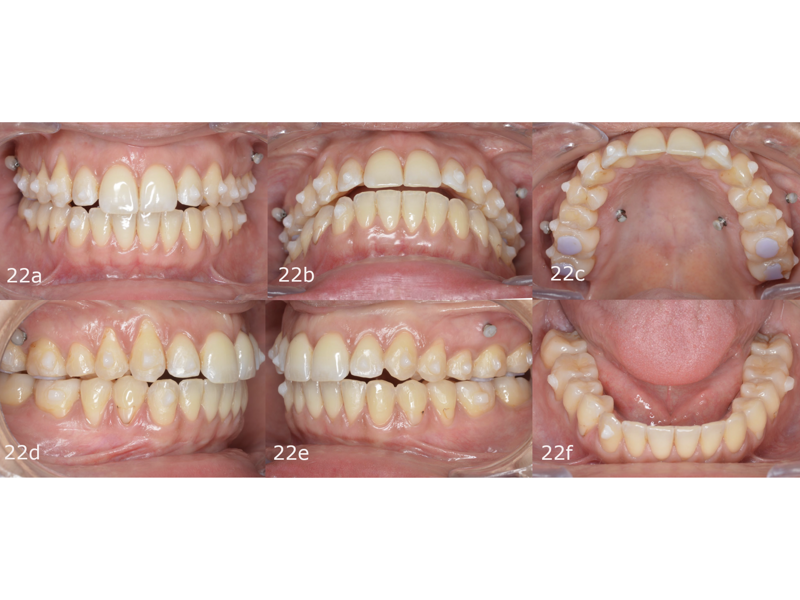

The second phase of treatment began with the placement of new attachments (Figs. 20–22) and consisted of 12 stages, during which we continued to intrude the maxillary molars, centre the mandibular midline and level the occlusal planes. This phase lasted for four months. The total treatment involved 32 stages over 11 months, and all the treatment goals were achieved (Figs. 23–25).

The final dental panoramic tomogram showed the correct levelling of the occlusal planes and root positions (Fig. 26). The final cephalometric tracing showed closure of the facial angle thanks to the posterior intrusion and mandibular auto-rotation (Figs. 27 & 28). Mandibular antero-rotation shortens the lower facial third, improving lip competence and ultimately the facial profile. The CBCT images of the TMJs showed the correct position of the condyles within the glenoid fossae (Fig. 29). When looking at the airway on the CBCT scan, we also saw an improvement of the patient’s airway (Fig. 30).